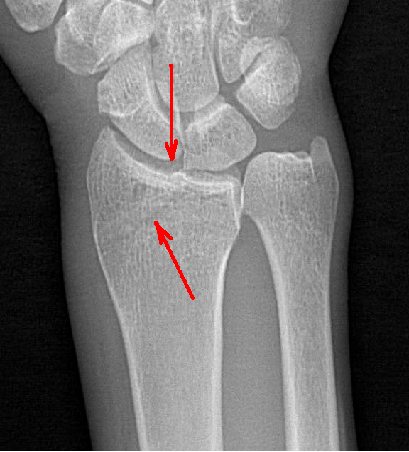

動(dòng)態(tài)DR具備高清攝像和動(dòng)態(tài)透視、實(shí)時(shí)高清點(diǎn)片等多種功能,對(duì)于隱匿性肋骨骨折的診斷優(yōu)勢明顯。